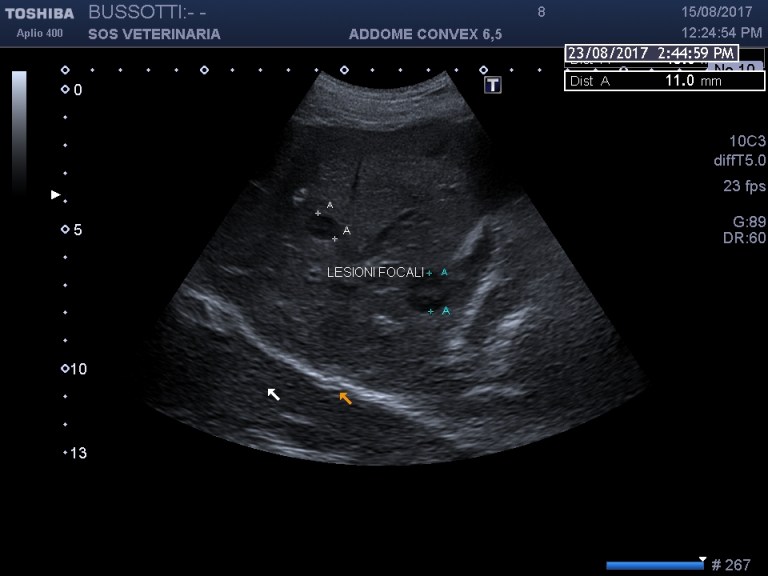

Evidenti alterazioni epatiche, colpisce la lesione focale a bersaglio,l irregolarita’ del profilo lobare ,il volume stimato aumentato ,la difficolta’ ad evidenziare le aree ventrali che sembrano essere ipoecogene e irregolari ,nel filmato verso gli ultimi frame si apprezza una massa retrogastrica verosimilmente linfocentrica meno probabile l interessamento del corpo pancreatico,

evidente la falda di fluido libero in addome campionata risultata essere ematica